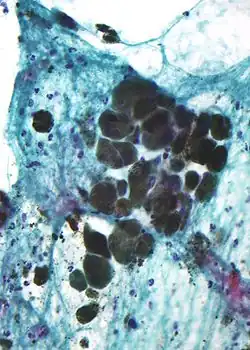

Aspect au microscope

Au microscope, la mélanine doit être distinguée des pigments produits par la destruction des hématies (hémosidérine).

Elle apparaît sous forme de granules bruns non-réfractiles de moins de 800 nm, alors que les granules de pigments sanguins sont plus gros, réfractiles et verts, jaunes ou brun-rouge.

Une solution diluée de permanganate de potassium fait disparaître la mélanine.